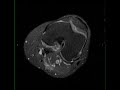

Pigmented Villonodular Synovitis Knee

35-year-old male with chronic left knee pain. The images demonstrate a proton density isointense, STIR mildly hypointense lesion with scattered regions of signal loss. The lesion heterogeneously enhances and is intimately associated with the posterior cruciate ligament. These imaging findings are characteristic of pigmented villonodular synovitis or PVNS for short. PVNS is a benign proliferative condition affecting the synovial membranes of joints, bursa, or tendons. It results from neoplastic synovial proliferation with villous and nodular projections with scattered hemosiderin deposition. It is most common monoarticular. Occasionally, PVNS can look like aggressive neoplasms such as rhabdomyosarcoma, synovial sarcoma, or epithelial sarcoma.